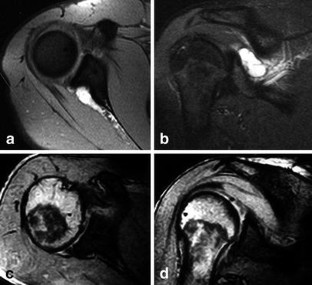

We evaluated an all arthroscopic technique for treating suprascapular nerve entrapment by cyst formation in the spinoglenoid notch. Eight patients showed positive MRI and EMG findings with clinical sign of weakness and pain and with atrophy of the muscle. All patients underwent an all-arthroscopic procedure. The patients were evaluated preoperatively and 6 weeks and 3 months postoperatively and for the latest follow-up by clinical examination, MRI, and EMG. All patients improved in terms of pain, strength, and function. We found six superior labrum anterior and posterior (SLAP) lesions. In these patients the cyst was drained, and the SLAP lesion was repaired. In two patients there was no communication between the joint and the cyst, and therefore capsulotomy was performed and left open. The results of our study show that arthroscopic decompression of the suprascapular nerve can be achieved by an all arthroscopic technique if the cyst formation is located at the spinoglenoid notch.

Fig. 4

Fig. 5